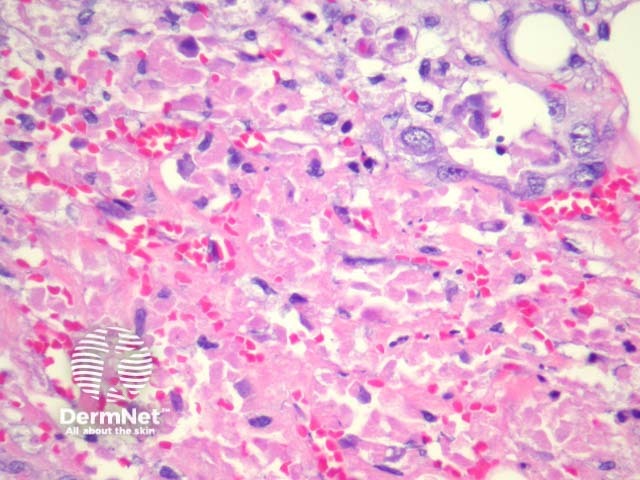

In sebaceous carcinoma, the tumour is generally dermally based with invasion into subcutis (figure 1) and native structures. Pagetoid invasion of the overlying epidermis may be seen. The tumour cells are basaloid with foci of sebocytic differentiation. Sebocytes are large cells with a multivacuolated clear cytoplasm (figure 2). Necrosis is common (figure 3, 4).

Figure 2